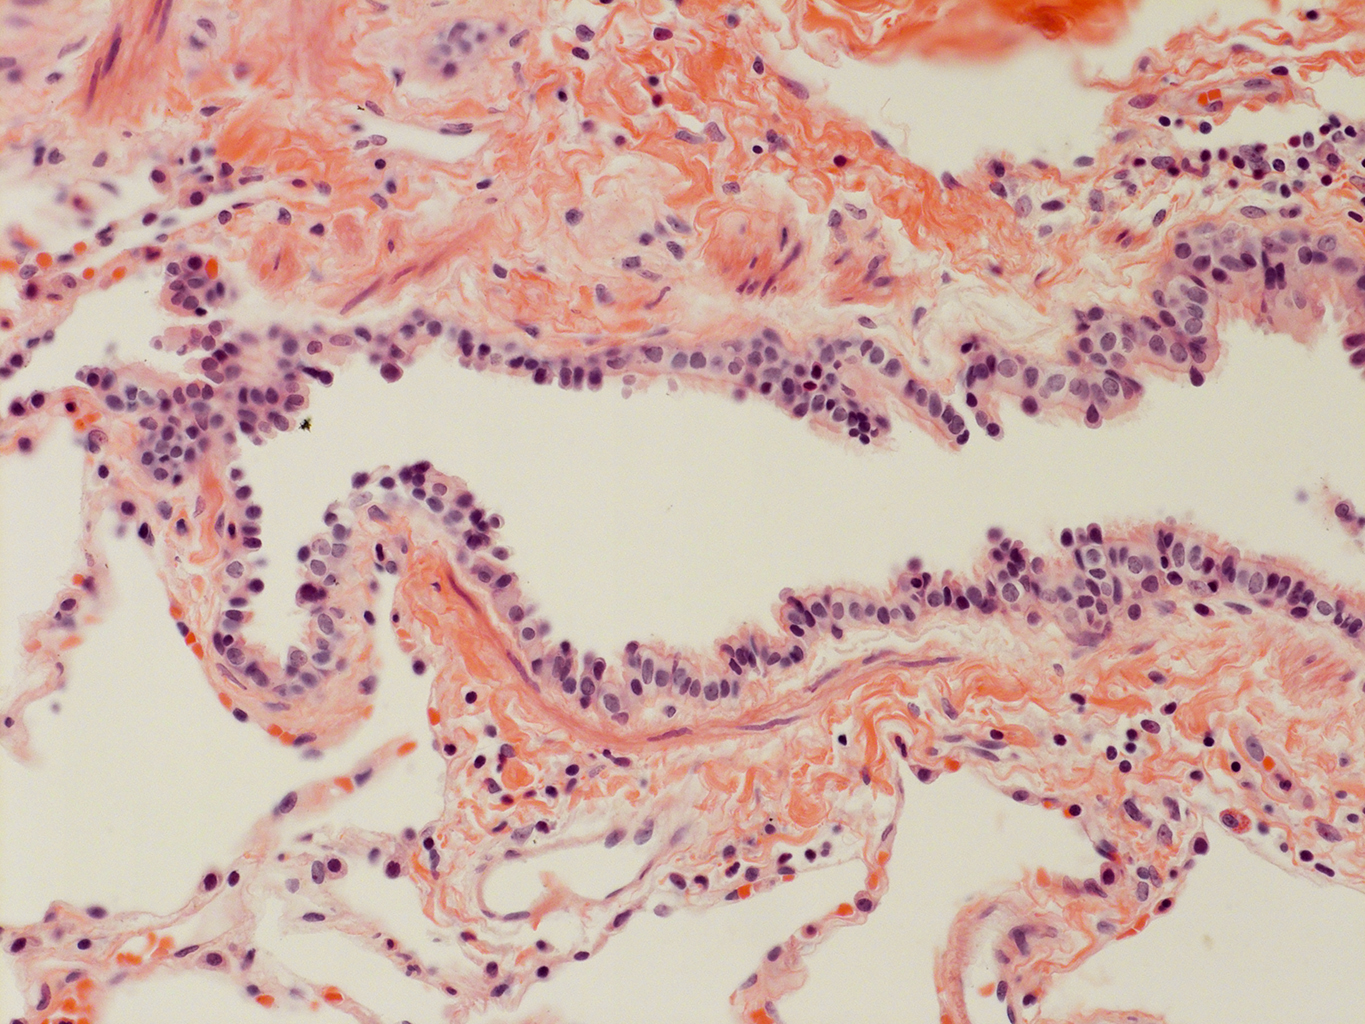

Donor tissue kindly provided by Dr. Scott Randell, University of North Carolina

Tissue Used:

LMHA-15-UNC-2017-12-19_D0037L.05HP_3_48

Gender: Male

Age:Â 43 Year Old

Race: Hispanic

Non-Smoker